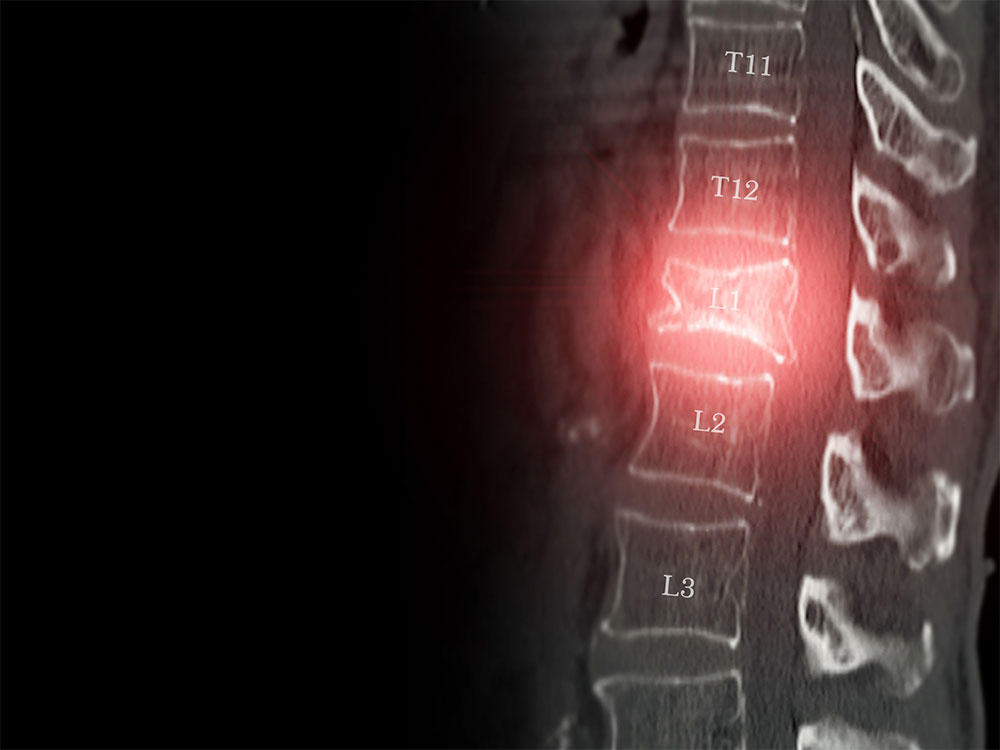

Vertebral compression fractures (VCFs), often associated with osteoporosis, are not merely a source of acute pain; they represent a direct threat to patient independence.

Vertebroplasty

This procedure involves the percutaneous injection of bone cement (PMMA) into the fractured vertebral body, with the aim of stabilising the vertebra and reducing pain.Kyphoplasty

This technique involves the insertion of a balloon, which, once inflated, aims to partially restore vertebral height before the infusion of bone cement.